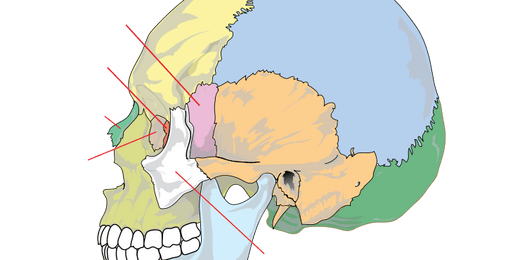

Jukbeen

De jukbeenderen (os zygomatica) vormen de wangen en de ...

Zeefbeen

De zeefbeendelen (pars os ethmoideus) bevinden zich tus...

Wiggebeen

Het wiggebeen is een van de schedelbeenderen en ligt la...

Voorhoofdsbeen

Het voorhoofdsbeen is een van de platte schedelbeendere...

Traanbeen

De traanbeentjes zijn twee van de kleinste botjes in he...